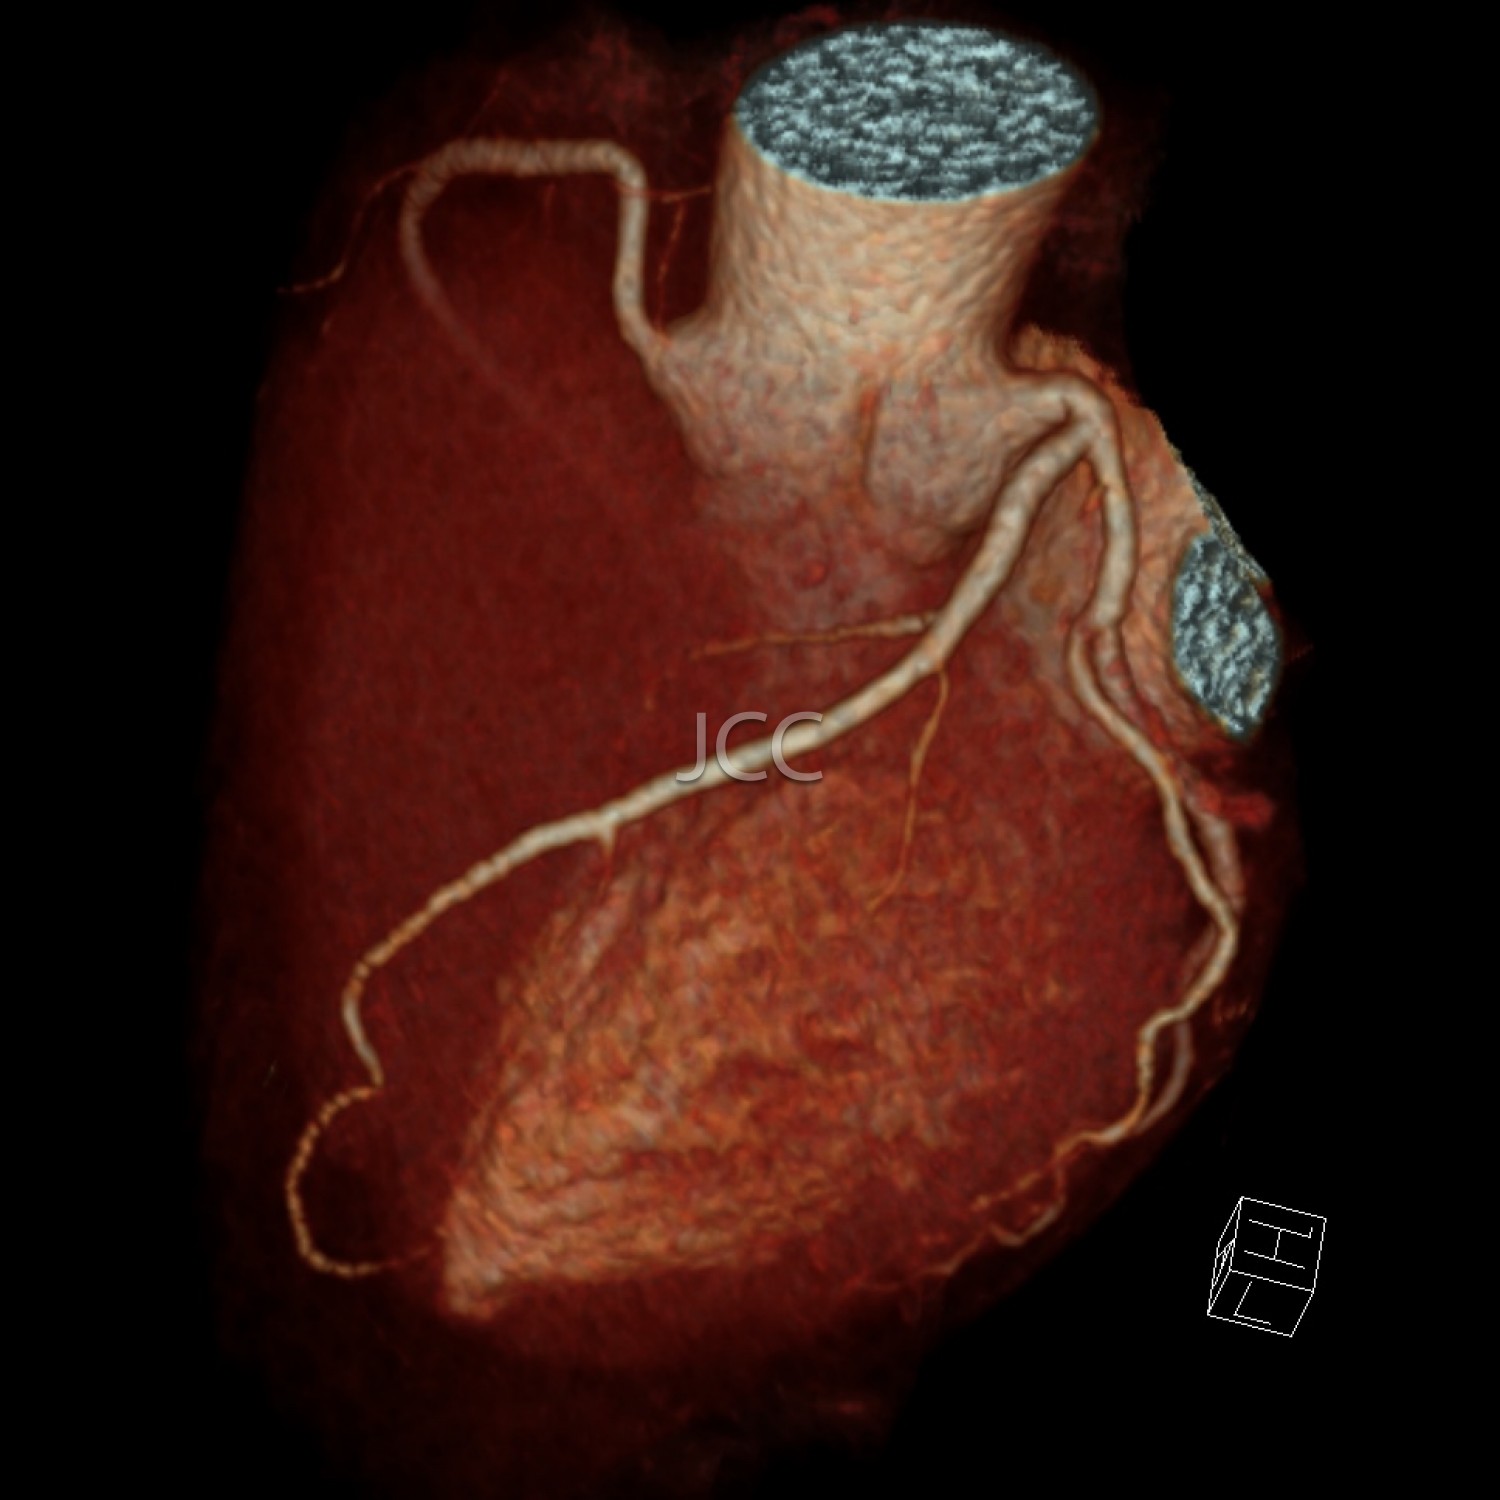

Tomografia Axial Computorizada - ANGIO TAC CORONÁRIAS

A Tomografia Axial Computorizada (TAC) - Dupla Energia - 256 cortes é uma técnica de diagnóstico que permite a avaliação de várias partes do corpo humano, incluindo pulmões, fígado, pâncreas, rins, coração, estruturas vasculares e estruturas ósseas.

Os nossos equipamentos são todos de multicorte permitindo avaliação em alta definição e baixa dose de radiação incluindo o estudo das coronárias.